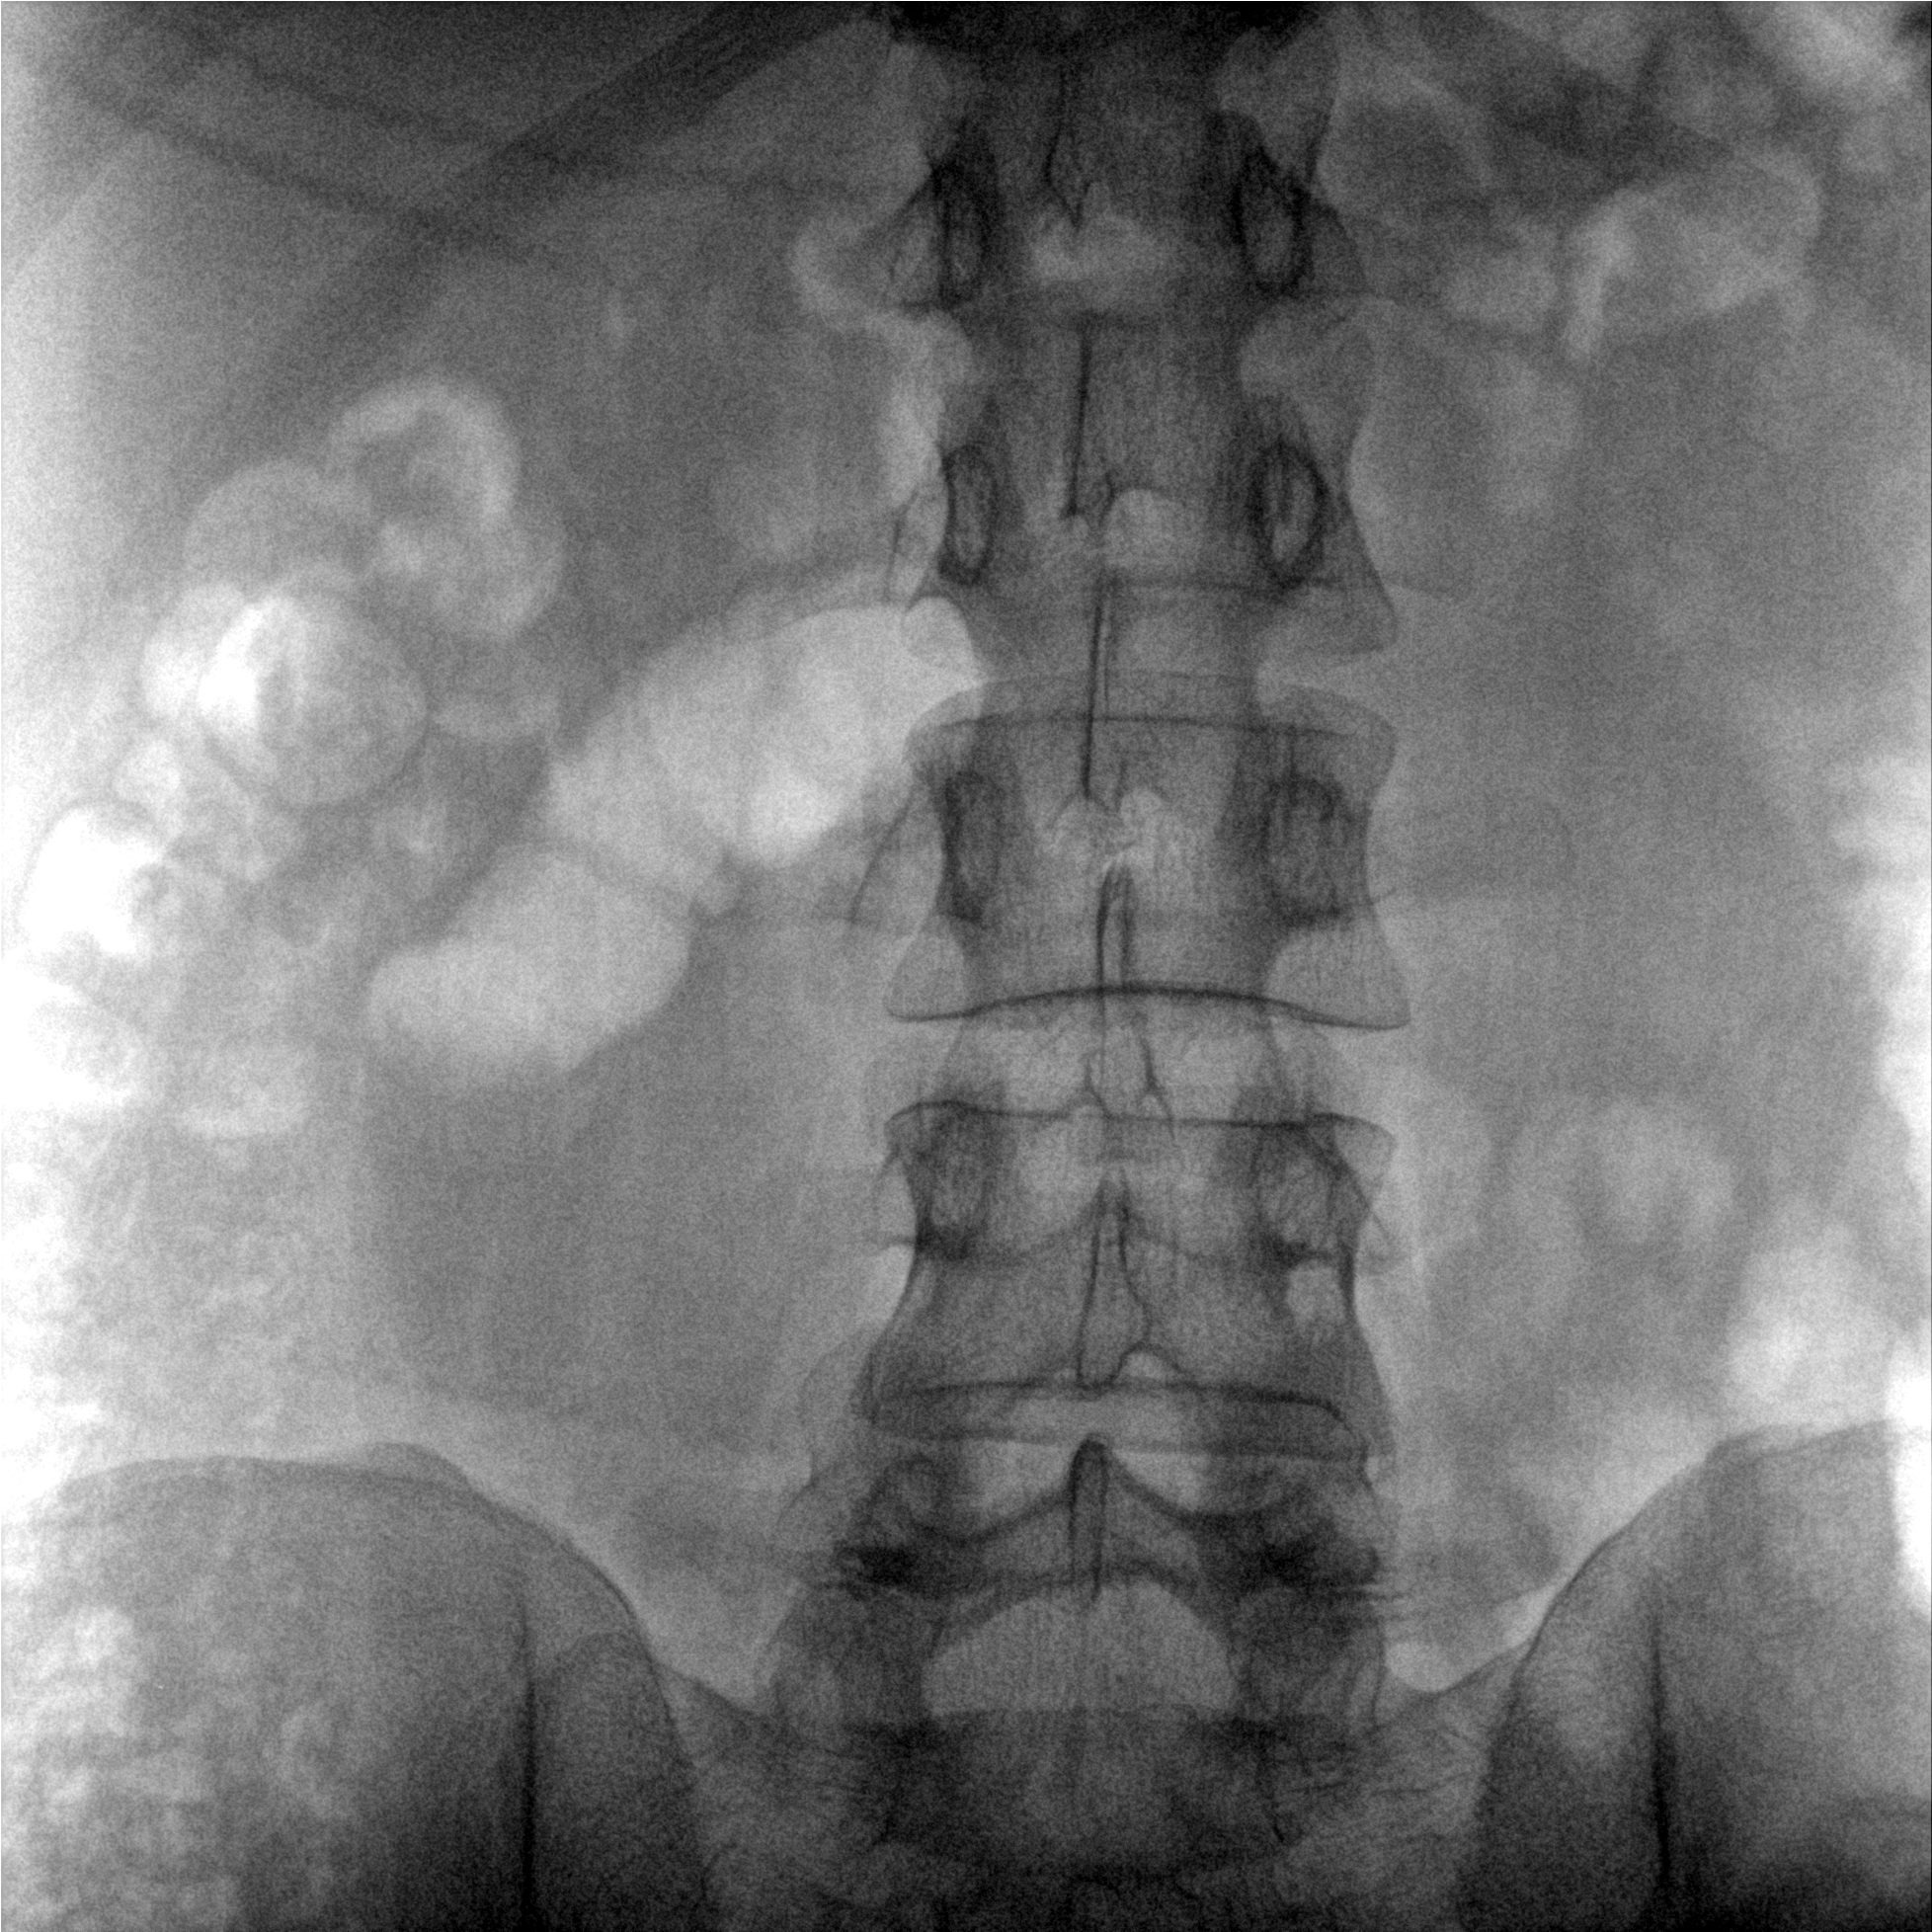

術(shù)中三維成像和橫斷面圖像提供多角度的手術(shù)診斷信息,輔助醫(yī)生進(jìn)行術(shù)中評(píng)估判斷,諸如骨折復(fù)位情況和內(nèi)植入螺釘?shù)某叽绾臀恢?,輔助手術(shù)更好地完成。

提供更大的術(shù)中三維成像視野,采集更多圖像信息,可一次拍全全段頸椎、全段腰椎、七節(jié)胸椎、雙側(cè)骶髂關(guān)節(jié)、股骨頭及單側(cè)盆骨。